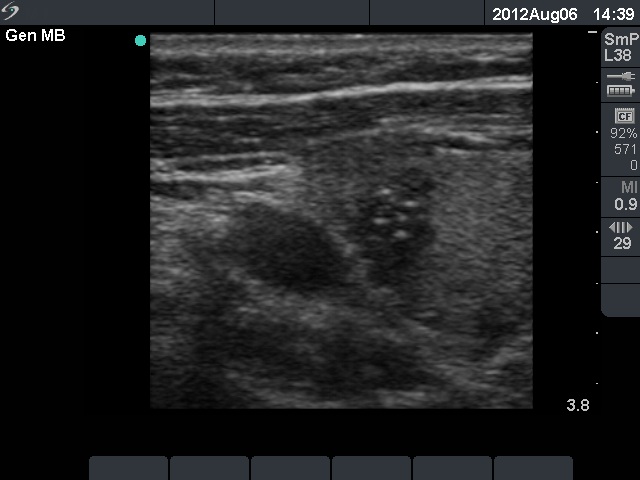

Papillary carcinoma (histological diagnosis) |

This case is less edifying or may be more edifying. Compared with the previous case, the granules here are less bright. Nevertheless, great proportion of them belong to punctate echogenic foci (arrows). It is worth to compare these with non-specific granules (arrowheads). |